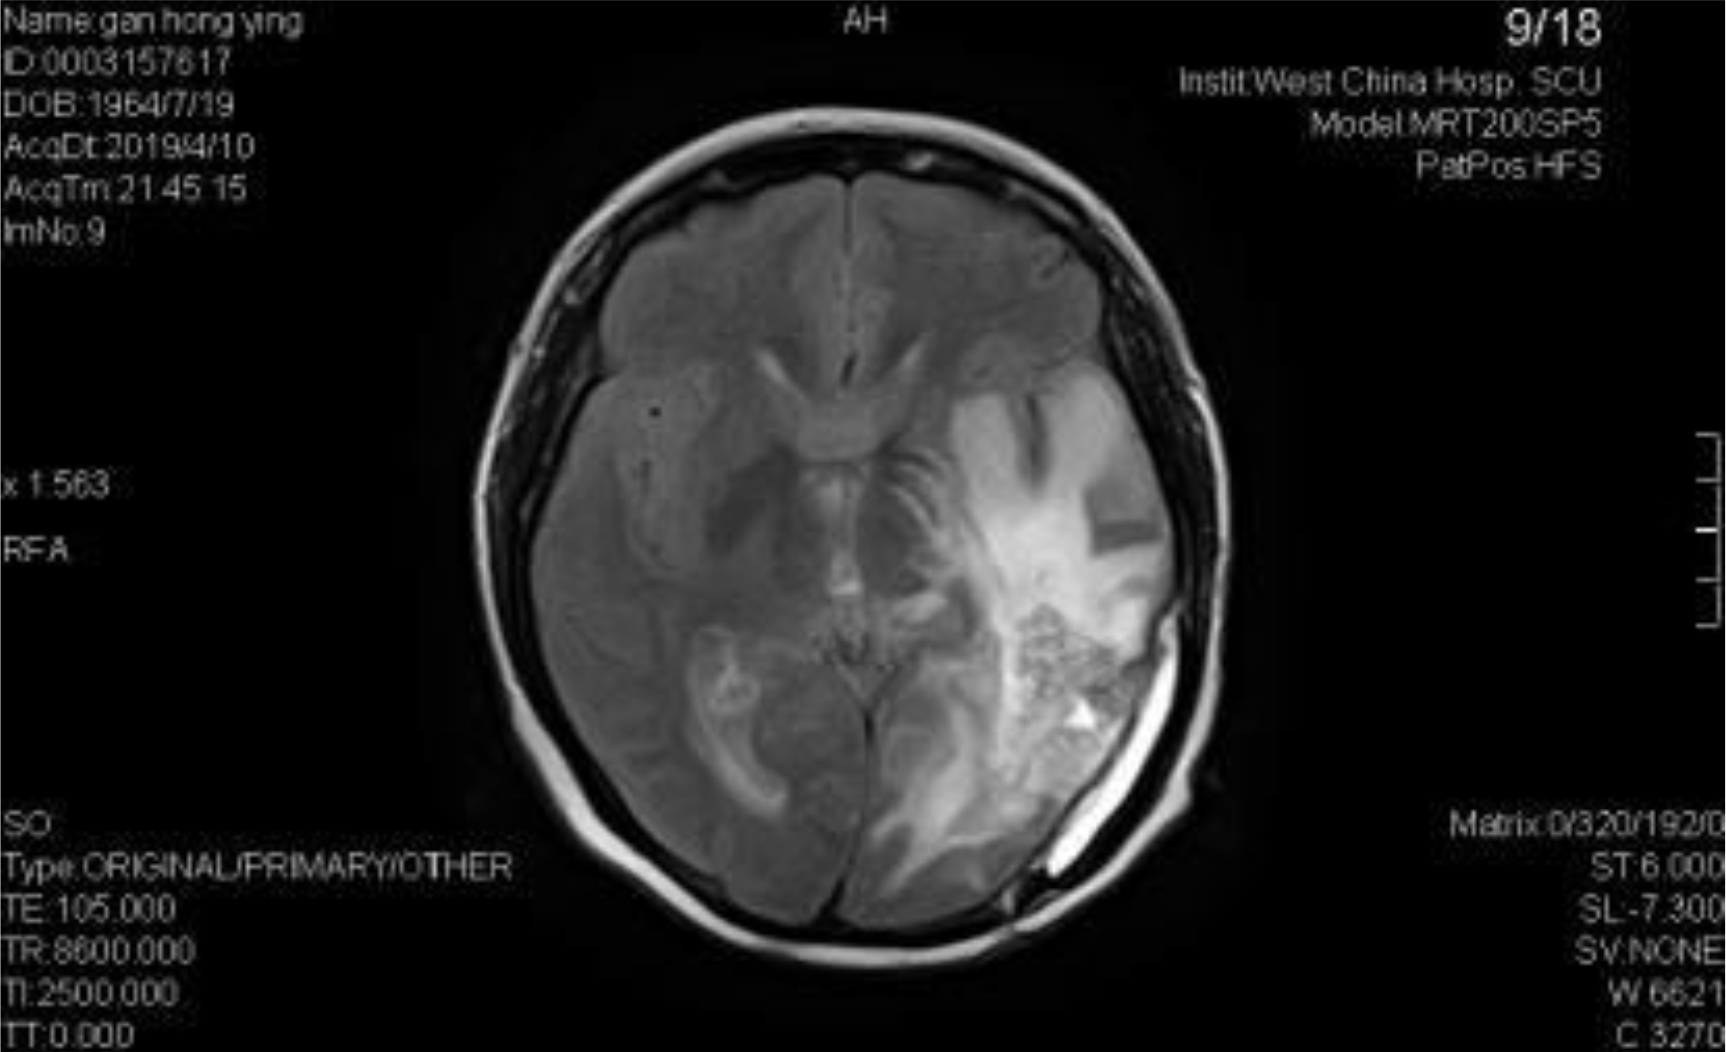

A 54-year-old female, developed a headache in December 2017. Examination showed that the left parietal occipital lobe occupied, and the first surgical treatment was performed, and the postoperative pathological diagnosis was glioblastoma. After operation, the patient received routine radiotherapy, 60Gy/33f, and temozolomide chemotherapy, 100mg/d (during radiotherapy), 300mg d1-5, q4w. In January 2019, the patient reexamined the MRI and found that the left temporal parietal space was occupied (Figure 1) and was operated again. The postoperative pathological diagnosis was still glioblastoma. The patient had occasional headache after operation, and the head MRI examination three months after operation indicated the progress of the disease (Figure 2). TTF was prepared to be used, and finally officially used the TTF treatment on July 4, 2019. The use time was relatively fixed, the utilization rate was 93%, and the compliance was good (Figure 3). During treatment, the patient developed allergic rash scattered on the scalp, mild itching, no ulceration and infection, and recovered quickly after topical application of antiallergic drugs. There had been several times that the patch temperature was too high, and the reasons are as follows: 1. The ambient temperature used was high (e. G. hot weather, direct sunlight, etc.). 2. The contact between the patch and the skin was not good. By instructing the patient to adjust the indoor temperature to about 24 °C, to use the headband or tape to strengthen the loose patch, to use the headband when sleeping at night, and to pay attention to clean the hair of the scalp every time, the situations had been significantly improved. Re-examination of the MRI in October 2019 showed that the condition was stable (Figure 4). Follow-up to 2020.1.23, the patient showed no symptoms of discomfort.

Figure 2